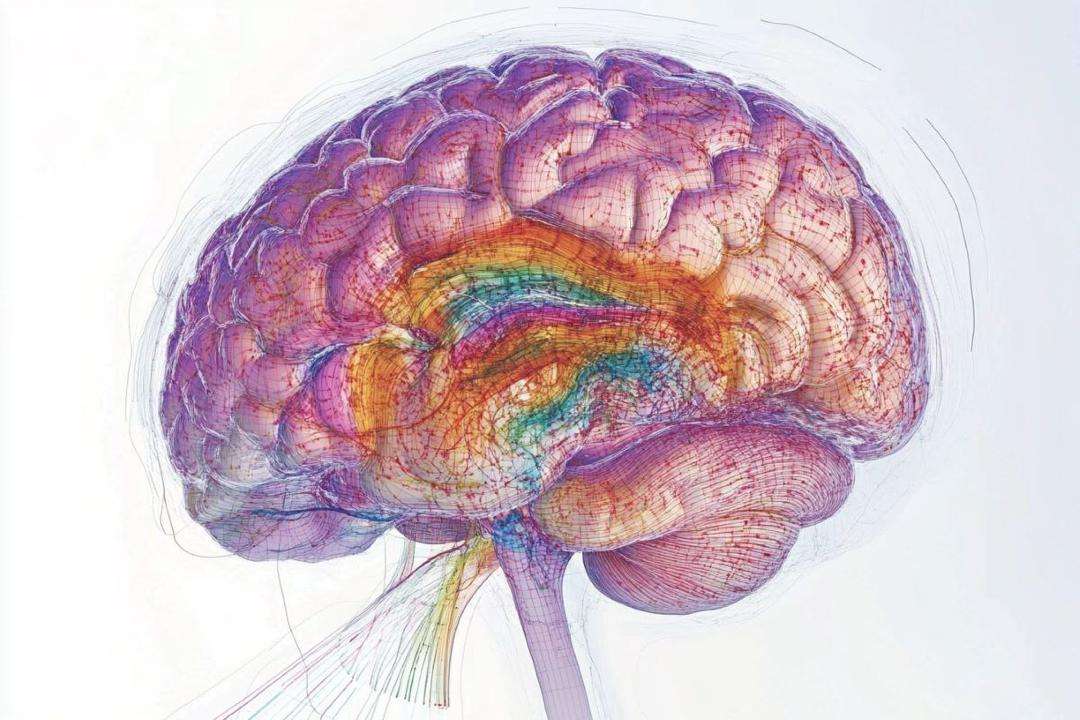

Investigadores identificaron un «suiche» cerebral que controla la edad y el envejecimiento, un hallazgo que podría revolucionar los tratamientos para frenar el deterioro cognitivo y mejorar la salud en la vejez.

La vicepresidenta sectorial para Ciencia, Tecnología y Salud Gabriela Jiménez Ramírez, compartió en su canal en Telegram, que este descubrimiento se basa en el estudio de ratones, que presentan estructuras cerebrales y genes similares a los humanos, lo que los convierte en un modelo animal clave para entender los procesos complejos del cerebro humano, refiere una nota de prensa del Mppcyt.

La también ministra para Ciencia y Tecnología informó que estos hallazgos fueron publicados en la revista Nature y son el resultado del mapeo genético de más de 1,2 millones de células de 16 regiones del cerebro de ratones jóvenes (de dos meses) y viejos (de 18 meses).

La ministra Jiménez Ramírez explicó además que en el estudio, se analizaron ratones envejecidos, equivalentes a personas de mediana edad, y se identificaron docenas de tipos celulares que muestran alteraciones significativas en su expresión génica con el paso del tiempo.

Los investigadores observaron que los genes vinculados a la inflamación aumentan su actividad, mientras que aquellos responsables de la función y estructura neuronal tienden a reducirla.

Asimismo, señaló que identificaron una región específica del cerebro donde se concentran estos cambios genéticos relacionados con el envejecimiento. En esta área, las alteraciones son especialmente pronunciadas y las células están vinculadas al metabolismo, sugiriendo una conexión importante entre la dieta y la salud cerebral.

Este descubrimiento podría ser fundamental para el desarrollo de nuevas terapias destinadas a ralentizar o controlar el deterioro causado por la edad.